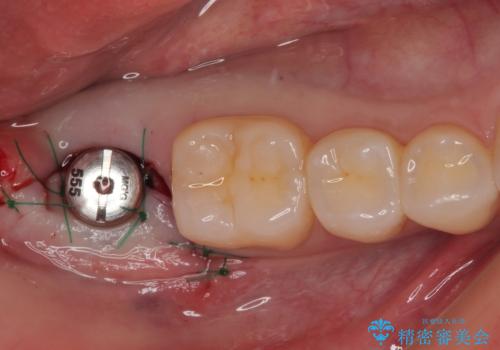

インプラント埋入と同時に仮歯を装着するために、事前に仮歯を用意し、速やかにインプラント埋入を行うこととしました。

術後にインプラントが骨から脱落することがありますが、特筆するトラブルなどなく、最短の3ヶ月で治療を終えることができました。